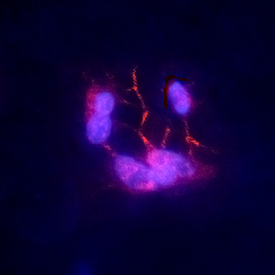

Researchers from the University of Nottingham have released two new publications using our primary human brain microvascular endothelial cells (cat. HEC02), brain pericytes (cat. HMP104), and brain astrocytes (cat. HMP202) to build an in vitro blood-brain barrier (BBB) model. Last week, we highlighted the first publication, where the impact of exposure to Substance P (SP) on the BBB was evaluated. You can check out the blog post to learn more.

Then, to our pleasant surprise, we saw the researchers cited our cells in another BBB related publication. This time, the investigators looked into some of the mechanisms behind neuroinflammation seen in ischaemic stroke and other disorders. They found that inhibition of Rho kinase neutralized the disruptive effects of TNF-α on BBB integrity. You can read the full study here.